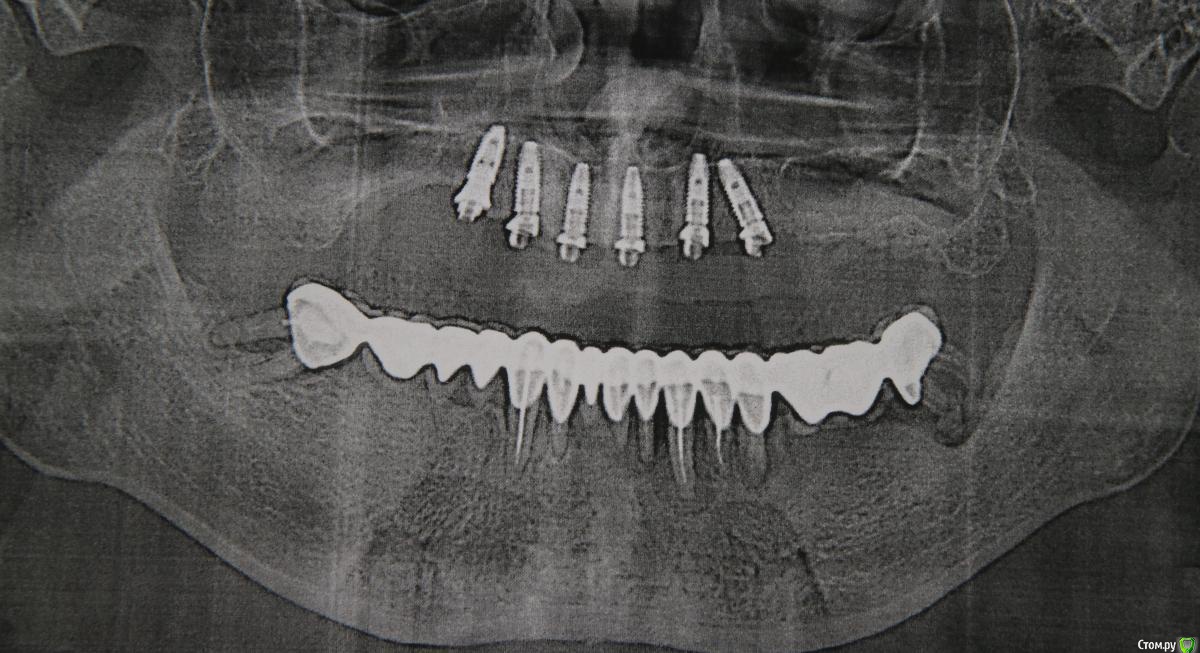

Александр07 Опубликовано 1 июля, 2020 Поделиться Опубликовано 1 июля, 2020 Коллеги доброго дня, пац 55-60 лет, хочет чтобы было красиво и крепко держалось, такая ситуация во рту, планируем операцию на вчКак видите примерно в обл 1.4-1.6 дефект по высоте, размышляю по поводу установки 1.1,1.3, 2.2,2.4 с расщеплением в обл 1.3, под протез на балке, Врем конструкция на импл , даже при условии что получится без большой подсадки, не рискнул бы- крупный мужчина, будет давать нагрузку, если ставить Мини импл то планировал бы позиции 2.1,2.5, 1 сегмент пока не ясно куда ставить ) По аугментации в обл 1.5-1.6, что посоветуете- делать /не делать, одновременно с фронтом или отдельно, или ограничиться тем планом по балке что написал выше , В обл 2.5-2.6 синус нужен trim.F286E467-8CC6-421B-ACE6-47434003E04E.MOV Ссылка на комментарий

Александр07 Опубликовано 12 августа, 2020 Автор Поделиться Опубликовано 12 августа, 2020 Коллеги вот как сделали в итоге, отправляю фото 1 Ссылка на комментарий